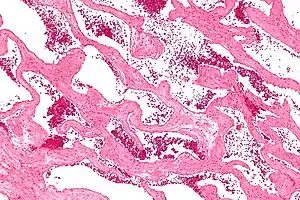

Hemangioma cavernoso, também chamado de angioma cavernoso, cavernoma ou cavernoma cerebral (quando se refere à presença no cérebro)[1][2] é um tipo de tumor vascular benigno ou hemangioma, em que uma coleção de vasos sanguíneos dilatados (aneurismas) formam uma lesão.[3]

A ressonância magnética GRE T2WI é o método mais sensível para o diagnóstico de hemangiomas cavernosos.[16] A ressonância magnética é uma ferramenta tão poderosa para o diagnóstico que tem levado a um aumento no diagnóstico de hemangiomas cavernosos desde o advento da tecnologia na década de 1980.[17] A aparência radiográfica é mais comumente descrita como em formato de "pipoca" ou "amora".[18] A tomografia computadorizada (TC) não é um método sensível ou específico para o diagnóstico de hemangiomas cavernosos.[19]

Na ultrassonografia, hemangiomas cavernosos no fígado apareceram como lesões homogêneas hiperecogênicas com realce acústico posterior. Na tomografia computadorizada ou ressonância magnética, mostra realce globular/nodular periférico na fase arterial, com porções de atenuação das áreas de realce. Na fase venosa portal, mostra realce centrípeto progressivo. Na fase retardada, mostra retenção de contraste. Ele mostra um sinal alto nas imagens ponderadas em T2.[20]